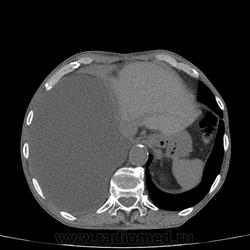

Самое интересное забыла показать- может это 100% навеет на мысль об опухолевом процессе, остеолитическая деструкция позвонка?

Коллеги, распада там нет, это вас медиастинальное окно подвело. В грудине тоже все в порядке. Да и компрессия позвонка "старая".

Небольшое количество увеличенных лимфоузлов, и те - не сказать, чтоб были очень крупными. От эмпиемы до онкологии... Умеренное количество жидкости в перикарде, толщиной слоя до 13-14 мм. При подобной картине не вижу смысла гадать по сжатому лёгкому, пишу так: массивный выпот справа, около 2500 мл, диафрагма оттеснена жидкостью каудально, печень (!!!) смещена каудально и вправо. Легкое справа значительно компрессировано жидкостью, оценка проходимости бронхов и состояния легочной паренхимы (кроме имеющейся эмфиземы) практически невозможна. Необходима пункция плевральной полости справа (цитология, ВК, посев на микрофлору и проч), КТ-контроль после эвакуации жидкости.